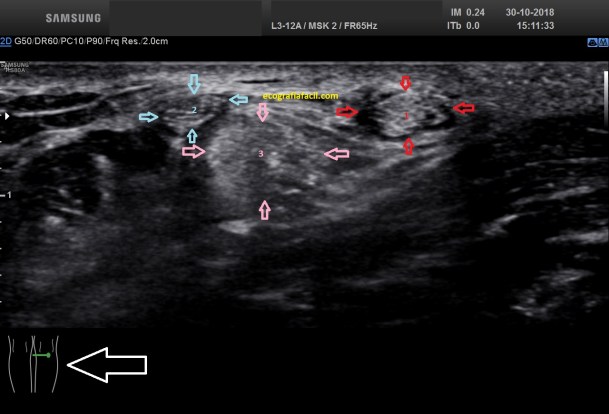

La imagen 3 y 4 son parte estudian en eje largo y corto las medidas de la lesión en los tres ejes del espacio, en ocasiones, podemos tener más de una lesión. Siempre super atentos si las lesiones son intra o extratesticulares.

En la imagen 5 podemos ver afectación testícular de las mismas características ecográficas, pero existen varios focos de lesión. imágenes 4 y 5 son pacientes distintos.

El aspecto de esta lesión, su semiología ya la has visto en estos dos casos diferentes, pero tienen en común, de modo general, hipoecogenicidad, heterogenicidad, bordes irregulares, con aspecto polilobulado y de tamaño y número variable.